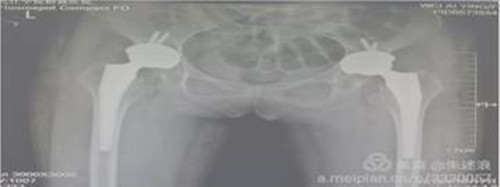

患者二十余年前开始出现髋关节疼痛,行走后疼痛加重,进行理疗、药物等保守治疗无明显效果,七个月前来临床医学院/附属医院就诊,行盆骨平片检查提示“双侧髋关节半脱位,股骨头缺血性坏死”。临床医学院/附属医院骨三科朱述浪主任带领手术团队为患者实施DAA微创手术,手术非常成功,患者在术后次日便能够负重行走,并保留正常的步态。

全髋关节置换术后康复尤为重要。在朱述浪主任的指导下,科护士长带领护理团队积极主动为患者提供康复帮助,从日常护理、助行装置使用等方面,逐步提高患者术后从事日常活动的能力。